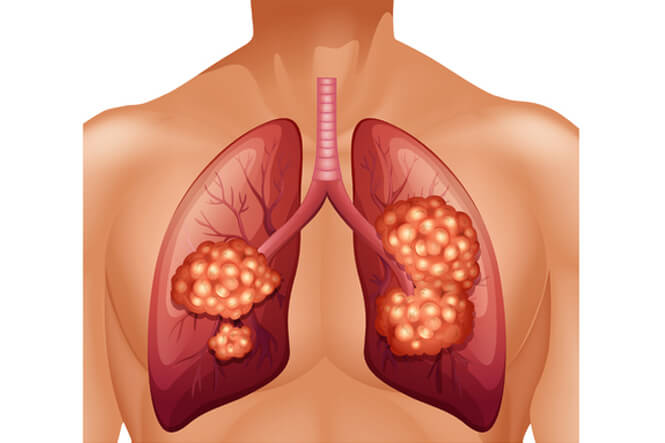

Respiratory diseases

Respiratory diseases are conditions that affect any of the processes involved with breathing. If you or someone you know are one of the 1 in 6 New Zealanders that lives with a respiratory condition, here you can find some useful information on how to manage the condition well.